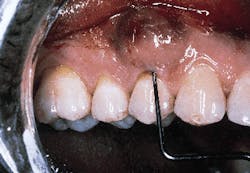

A patient with a periodontal abscess on the buccal of tooth #5 can be seen in photograph #1. Probing reveals a 6 mm pocket.

Photograph #1: An abscess is present on the facial aspect of tooth #5. Probing indicated a 6mm pocket.